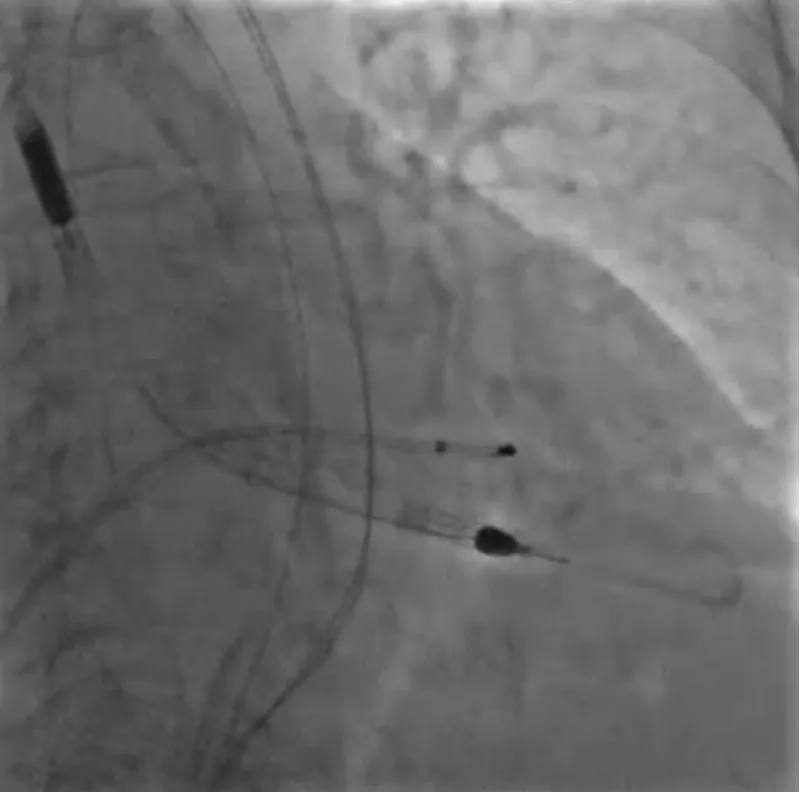

With the support of deep sedation, an angio-guided right femoral access was obtained, and a 12F introducer was advanced. We crossed the aortic valve with an Amplatzer left 1 catheter with a 0.035” wire and exchanged the wire with an extra-stiff Safari. We performed aortic Valvuloplasty with a Nucleus balloon 18 x 40 mm. (Figure 7) Then, we exchanged the wire and advanced an IMPELLA CP device, starting a protected PCI on LM. (Figure 8) An EBU 4.0 catheter was advanced, the stenosis was crossed on the Left Main (LM) and mid-Left Anterior Descending artery (LAD) using a BMW guide wire, and with the aid of a microcatheter a 0.014” Rotawire was positioned, followed by rotational atherectomy using a 1.5 mm burr on LM and mid LAD, (Figure 9) and a 2.0 mm burr on LM alone (Figure 10). This was followed by predilation with a 2.5 x 20 mm SC balloon and the implantation of a 2.5 x 32 mm Synergy drug-eluting stent (Figure 11). Then, the Left Main was predilated with a 3.5 x 12 mm NC balloon, and a 4.0 x 15 mm Xience Sierra drug-eluting stent was implanted and post-dilated with a 4.5 x 8 mm SC balloon (Figure 12). Immediate angiographic control confirmed a successful result. Then we removed the IMPELLA CP device and advanced a 14F e-sheath Edwards on the right femoral artery, crossed the aortic valve with a Safari extra-stiff wire, and performed a Sapien 3 23 mm valve implantation with a good angiographic result (Figure 13). Post-procedural echocardiographic and angiographic assessment confirmed the valve was correctly positioned, with no significant gradient and a minimal residual leak. The procedure was uneventful, and the patient was discharged on the fourth day with triple therapy: Aspirin 100 mg once daily, Clopidogrel 75 mg once daily, and Apixaban 2.5 mg twice daily. At the quarterly follow-up, the patient reported hospitalization for anemia, requiring a transfusion of 3 units of packed red blood cells. Endoscopic exams were negative, and hypochromic, normocytic anemia persisted. Given the patient’s CHA2D2-VASc score of 5, HAS-BLED score of 4, and recent dual Drug-Eluting Stent (DES) implantation, she was admitted for left atrial appendage percutaneous closure. Before this procedure, a repeat coronary angiography showed good results in the previously implanted stents (Figure 14). Subsequently, through a right femoral percutaneous approach using a 12F introducer, a 22 mm Amulet device was positioned for left atrial appendage closure (Figure 15). The procedure was completed without complications. At the 4-year follow-up, the patient presented in good hemodynamic status, with an echocardiographic ejection fraction of 55%. She continued on clopidogrel 75 mg once daily therapy.

Figure 9: Rotational atherectomy with Rotablator Burr 1.5 mm on LDA.

Figure 10: Rotational atherectomy with Rotablator Burr 2.0 mm on LM.